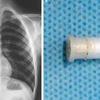

Moški je najprej prejel injekcijo za blažitev otekline, kirurg je poskusil s kleščami, vendar zaman. Sledil je, kot so zapisali, skrajni ukrep, ko je moral zdravnik poprijeti za industrijsko krožno žago za rezanje kamna. Ob tem so mu s hladno solno kopeljo hladili penis. Z Boschevo GDC 120 žago, katere rezilo se zavrti vrti do 200 krat na sekundo, so rezali 15 minut, preden so jekleni ležaji popustili, povzema DailyMail.